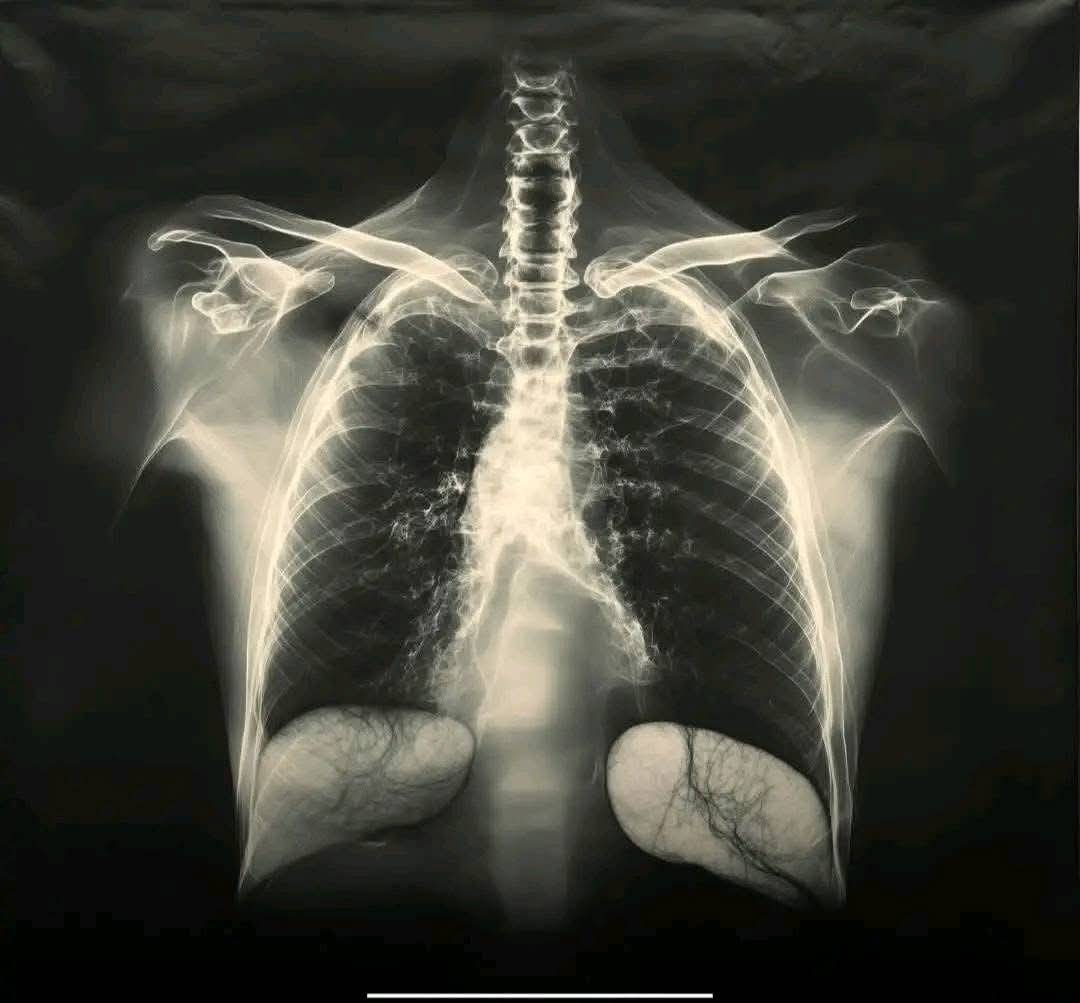

Sinds de start van de COVID-19-vaccinatiecampagnes is er één vraag die regelmatig wordt gesteld: kan het vaccin schadelijk zijn voor de longen? Sommige mensen melden kortademigheid of ademhalingsproblemen na de injectie. Deze zorgen verdienen een duidelijke uitleg, aangezien longgezondheid sinds de pandemie een groot aandachtspunt blijft.